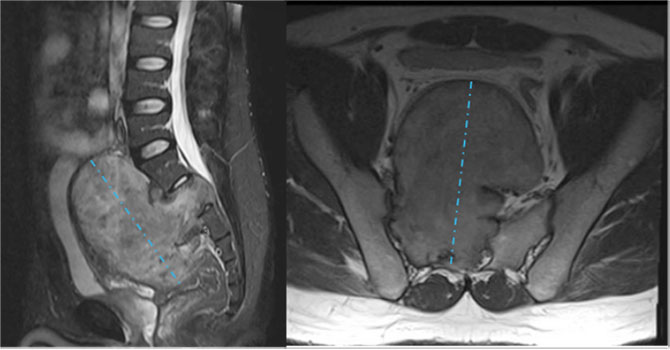

37岁的黄先生(化名)作为家中独子,是年迈父母的精神支柱和整个家庭的顶梁柱。3个月前的一次体检中,磁共振检查提示盆腔内生长着一个体积达18×16×12厘米的巨大肿瘤,如同一颗随时可能引爆的“炸弹”。肿瘤起源于骶2神经根,前方紧贴膀胱,侧方包裹输尿管与右侧髂内动静脉,后方毗邻直肠,多家医院均因手术风险极高而建议转院治疗。

抱着最后一丝希望,黄先生来到我院脊柱外科门诊。陈崇博士接诊后,立即组织全科讨论:肿瘤体积巨大、解剖关系极其复杂,如果手术,可能会损伤大血管,导致致命性出血的风险极高,还需兼顾保护马尾神经功能。患者如此年轻,若神经功能受损导致大小便失禁或下肢瘫痪,对这个家庭将是毁灭性打击。面对挑战,脊柱外科团队决定“亮剑”,3D打印实验室紧急制作肿瘤模型,脊柱外科、泌尿外科、麻醉科、输血科、重症医学科等多学科专家围绕模型反复推演,精准设计"前-后-前"联合入路方案,在虚拟空间预演每一个分离步骤,力求实现肿瘤完整切除与神经功能保留的双重目标。